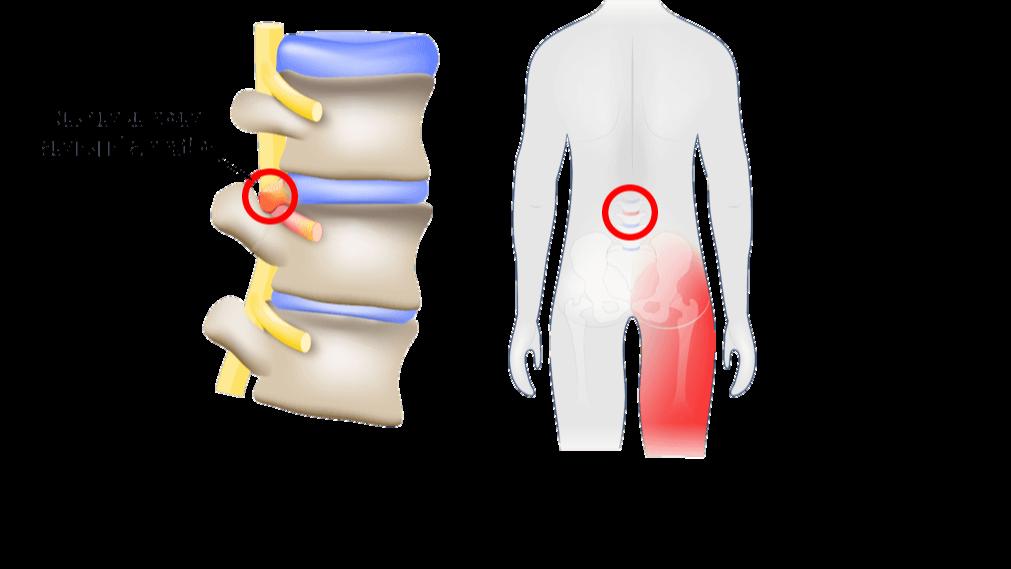

Whilespinalfusionaimstostabilizethespinebyfusingvertebrae, DiscSeeltargetsdiscdegenerationandassociatedtearsorleaks, sealingfissuresandpromotingtissueregeneration.

Withsmallerincisionsandreduceddisruptiontosurroundingtissues, DiscSeelboastsshorterrecoverytimes,lesspostoperativepain,and quickerreturnstonormalactivities.

DiscSeelmitigatestheriskoffusion-

relatedcomplicationsoften associatedwithtraditional approachesbypreservingspinal mobilityandflexibility.

Forindividualsseekingaminimallyinvasive,targetedsolutiontodiscogenic backpain,DiscSeeloffersacompellingalternativethatprioritizespatient comfortandlong-termoutcomes.